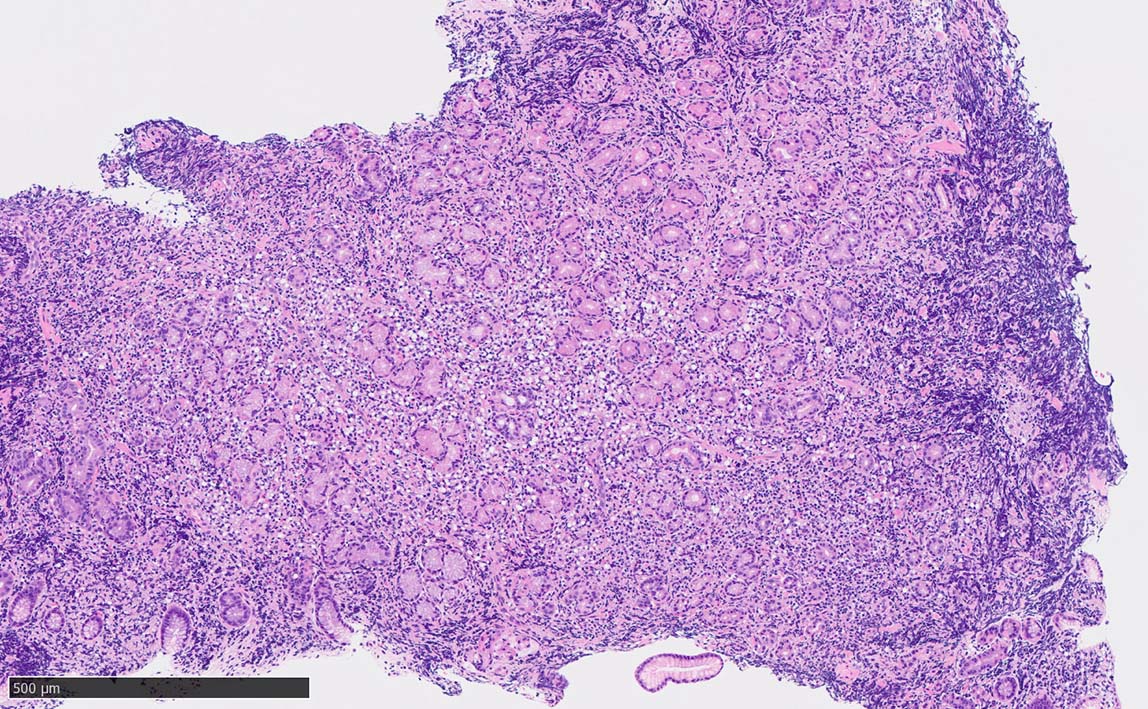

60 year-old male. 胃生検組織

stomach biopsy, HE

腺窩上皮

x200 HE